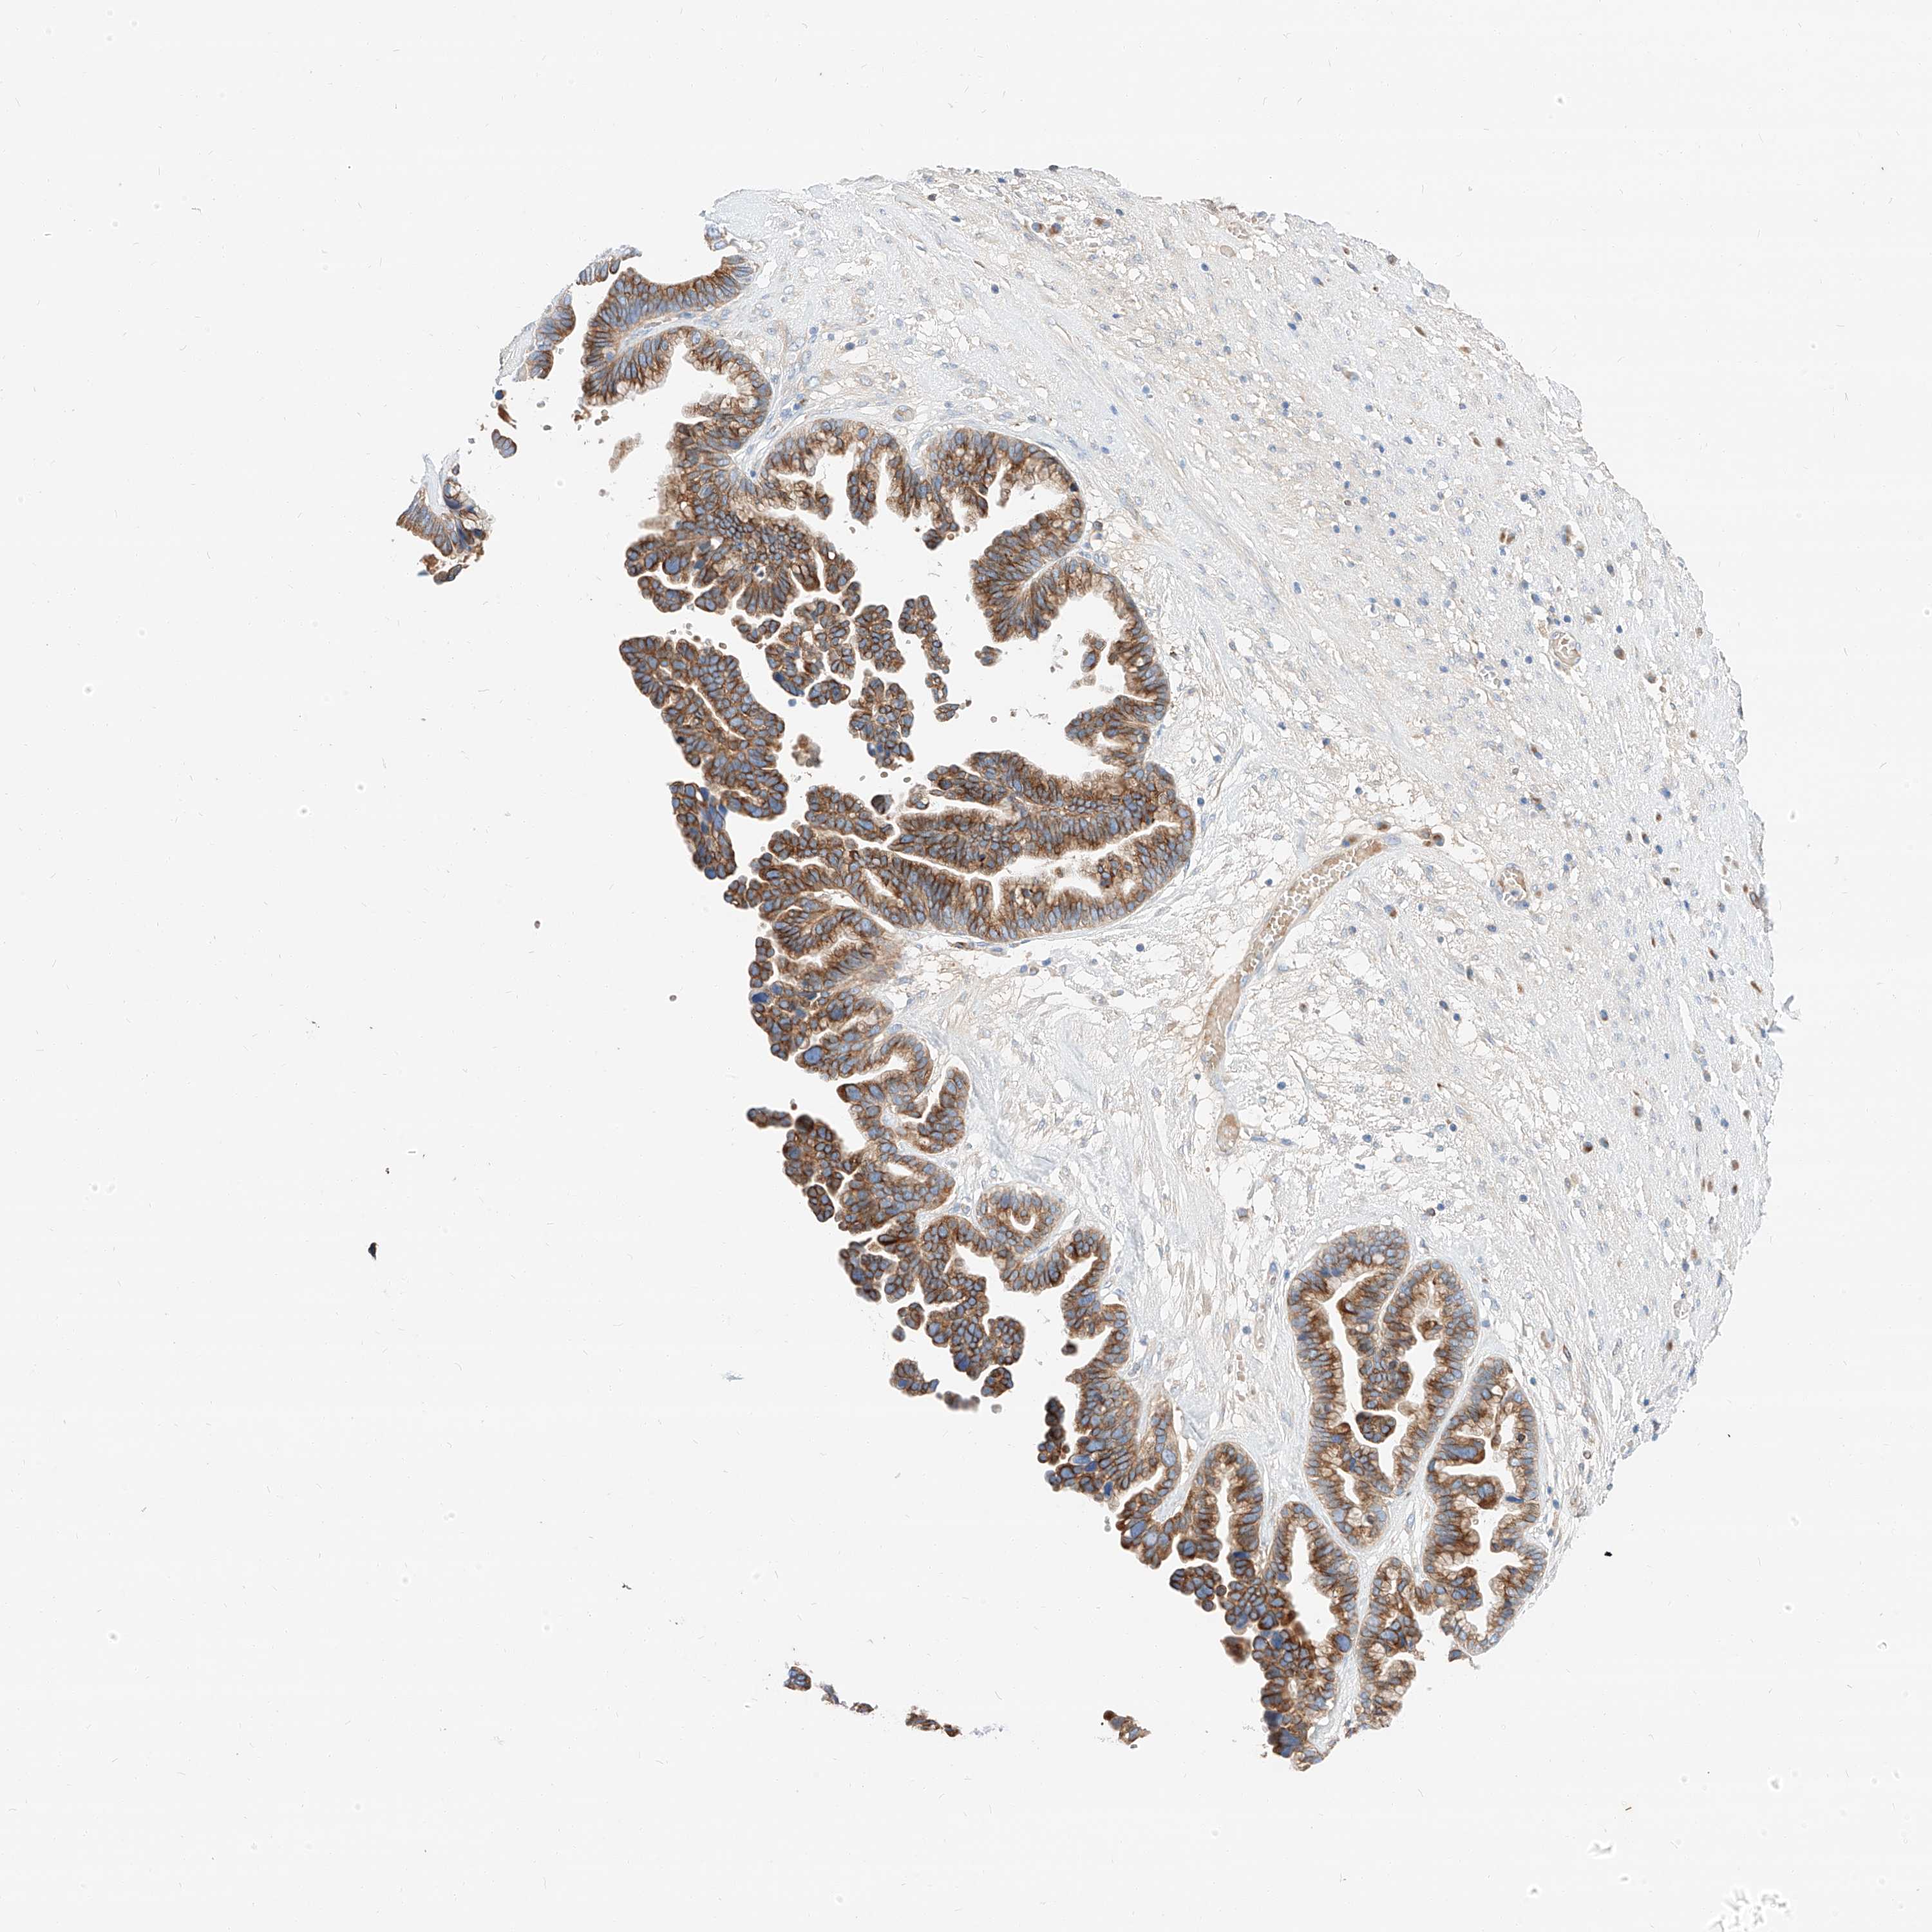

OVARIAN CANCER - Protein expressioni

A mouse-over function shows sample information and annotation data. Click on an image to view it in a full screen mode. Samples can be filtered based on level of antibody staining by selecting one or several of the following categories: high, medium, low and not detected. The assay and annotation is described here.

Note that samples used for immunohistochemistry by the Human Protein Atlas do not correspond to samples in the TCGA dataset.

Antibody stainingi

Antibody staining in the annotated cell types in the current human tissue is reported as not detected, low, medium, or high, based on conventional immunohistochemistry profiling in selected tissues. This score is based on the combination of the staining intensity and fraction of stained cells.

Each image is clickable and will lead to virtual microscopy that enables deeper exploration of all samples and also displays staining intensity scores, fraction scores and subcellular localization as well as patient and tissue information for each sample.

Antibody HPA029712

Antibody HPA029713

Cystadenocarcinoma, serous, NOS

Carcinoma, endometroid

Cystadenocarcinoma, mucinous, NOS

Carcinoma, NOS